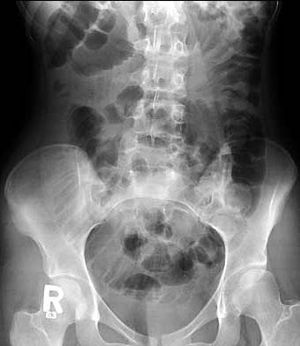

A 16-year-old female patient with repeated vomiting. First X-ray of the abdomen shows multiple dilated small bowel loops, represent distal small bowel obstruction. CT of the abdomen done for further evaluation.